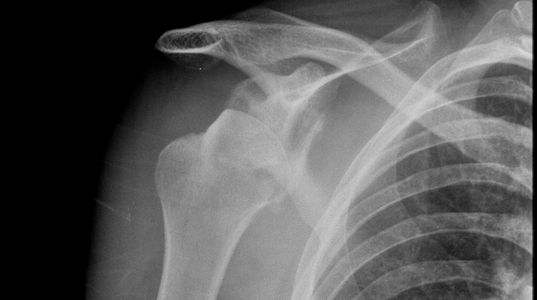

Not every greater tuberosity fracture is the same. An avulsed GT fragment (top picture) has a different mechanism (pull) to a comminuted fracture (impact) and the risk of an underlying fracture line is infinitely higher with the latter type. Turning a humeral neck fracture from undisplaced to displaced with your attempted manipulation is definitely one to avoid. There is a great case example published by Jung Ho Park in which a 74-year old man fell from a motorbike and landed on his left shoulder (impact mechanism). If you look at the initial films (above pics) the GT is not very displaced but is definitely comminuted – mechanism and GT# type now both suggest impact with risk of underlying humeral neck #. Traction/counter-traction technique had predictable results, but even using a gentle zero position may have had the same effect.

Take home message – if your patient is at higher risk of underlying pathological fracture, has an impact mechanism, or an impact fracture pattern of GT then CT to exclude an undisplaced proximal humeral fracture before you manipulate.